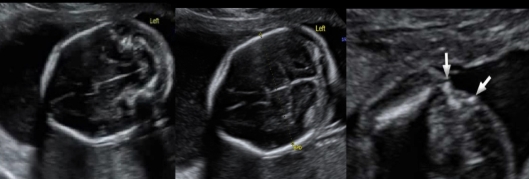

which shows funneling of the cervix

a) C + D

b) A + B

c) D only

d) B, C, D